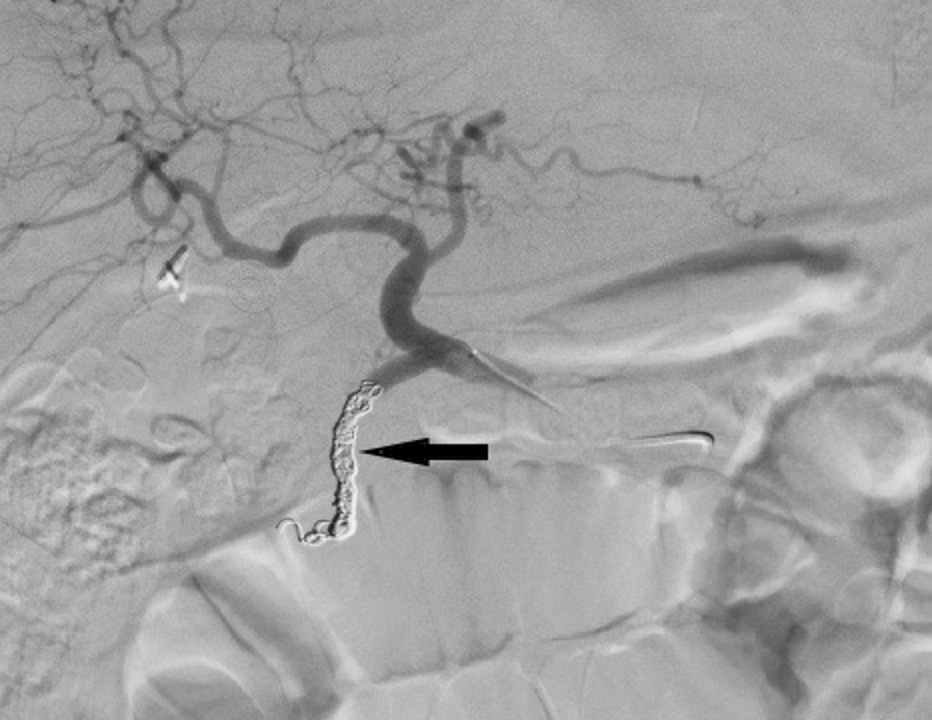

From www.researchgate.net

Angiogram performed after selective coil embolization of the Coil Embolization Of Gda The gastroduodenal artery (gda) is frequently embolized in cases of upper gi bleed that has failed endoscopic therapy. Gastroduodenal artery (gda) pseudoaneurysms are among the rarest forms of vapa (<2%). We report successful coil embolization of a ruptured gda pseudoaneurysm in a patient with massive gi. The gastroduodenal artery (gda) is frequently embolized in cases of upper gi bleed that. Coil Embolization Of Gda.